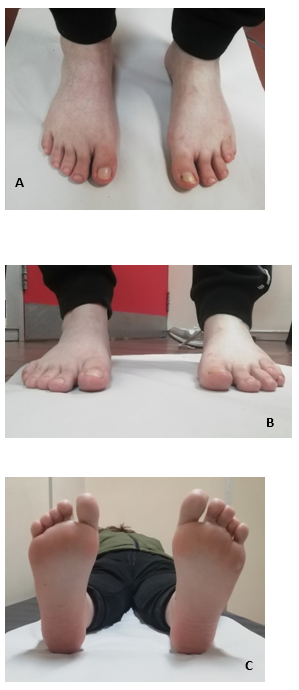

CASO 1: Paciente de 40 años, sexo femenino, portadora de un acortamiento congénito del cuarto metatarsiano bilateral y asimétrico. Consultó por un problema estético y metatarsalgia a nivel de la cabeza del cuarto metatarsiano del pie izquierdo. Al examen físico se destaca que tiene un cuarto radio corto, con un dedo elevado, sin lesiones en dorso, flexible y subluxado con un leve varo. Sin alteraciones neuro-vasculares distales y pulsos presentes. El retropie tenía alineación neutra. Las articulaciones tibiotarsiana y subastragalinas eran móviles e indoloras. No se observan desviaciones asociadas de los otros dedos, que son flexibles.

En la planta del pie se constata una hiperqueratosis a nivel de la cabeza del cuarto metatarsiano. El pie derecho, era asintomático, si bien tenía un cuarto radio corto de menor magnitud con respecto al otro pie, el dedo estaba en mejor posición, sin callosidades. (Figura 1).

Figura 1: A y B: frente y perfil. Presentación clínica del paciente. Se observa una braquimetatarsia del cuarto radio.

CASO 2: Paciente de sexo femenino, 23 años, presenta un acortamiento congénito del cuarto metatarsiano, bilateral y simétrico, acompañado de un acortamiento del cuarto metacarpiano de ambas manos. No presenta familiares de primer ni segundo grado con dichas alteraciones. Consulta por problemas estéticos del pie, dolor en la bipedestación y una metatarsalgia de trasferencia de los metatarsianos centrales, con hiperqueratosis en planta a dicho nivel. El cuarto dedo estaba subluxado, flexible, sin lesiones en dorso, no siendo doloroso a la palpación. No presentaba compromiso vásculo-nervioso distal. La alineación del retropié era neutra y los pulsos distales estaban presentes. Las articulaciones tibiotarsiana y subastragalinas eran móviles, indoloras y simétricas. El resto del examen físico era normal. Se clasifica según Lamm en 4 AC. 3 (Figura 7)

Figura 7 A y B: Presentación clínica de la paciente. Se observa la braquimetatarsia del cuarto radio, un segundo y tercer dedos largos.